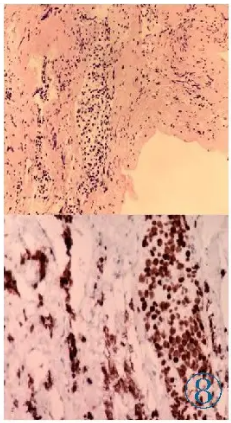

及抗结核治疗后症状无改善,为进一步明确病变性质,患者行腰椎髓外硬膜病灶穿刺活检术。活检组织病理显示:光镜下组织内小灶细胞较密集,细胞异型性明显,结合免疫组化表现,符合软脑膜弥漫性中线胶质瘤

(Diffuse midline glioma,DMG),WHOⅣ级(图8)。免疫组化:CD163(-),Olig2(弥漫+),GFAP(弥漫+),SSTR2(-),H3K27M(弥漫+),KI-67(+,约70%),S-100 (-),LCA(-)。分子基因测序提示H3F3A基因K27M突变阳性。患者拒绝进一步治疗,出院半年后死亡。

图8 活检组织病理示镜下可见脊膜软组织中小灶细胞聚集(HE),瘤细胞H3 K27M弥漫强阳性(En Vision法)。